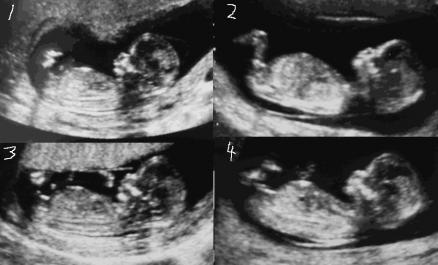

Exact age: 13w+1

I keep thinking #2 is a boy and #4 is a girl. Your opinions and comments would be greatly appreciated. TY.

Something makes me think girl i think in pic2 baby is slightly tilted bottom up if baby was lying flat as such the nub would look straighter.... Tricky cos then pic 3 makes me think boy !!

I think boy, nub looks slightly tilted upwards.

all pics looks like a boy at 13 weeks i would say boy :DS: